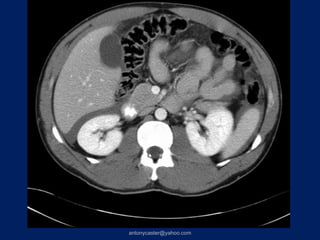

CASO 1

• Paciente varón, 37 años de edad,

etilismo agudo, caída a una zanja.

• RTS: 7,84   NISS: 9